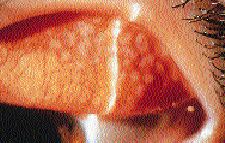

Phlyctenular keratoconjunctivitis (PKC) is characterized by a raised nodule of lymphocytes (phlyctenule) at the limbus. Incidence may increase slightly during the spring. Phlyctenular conjunctivitis is usually the first and only sign of this disease. It is characterized by a local area of hyperemia, usually near the limbus but may be entirely on the conjunctiva. Nodules can be single or multiple, found on the bulbar or the palpebral conjunctiva and on the lid margin. Phlyctenules, which appear within a day or two in the center of the hyperemic area and quickly elevate to a millimeter or more above the surrounding conjunctiva, are gray or yellow-white and avascular (Fig. 8). After several days, a small dimple may appear at the apex, which then gradually spreads to shrink the nodule. Symptoms in cases limited to the conjunctiva are relatively mild and include itching, tearing, photophobia and irritation. Phlyctenular keratitis has a tendency to break down and form a marginal ulcer, which should not be confused for an infectious process in contact lens wearers. Symptoms are usually more severe and can include blepharospasm. The healing response will leave a scar or fasicular ulcer. A pannus is possible and is the result of diffuse infiltration or recurrent phlyctenules that develop close to the blood vessels and progress centrally. Super-infection is always a concern, so appropriate antibiotic coverage is essential.